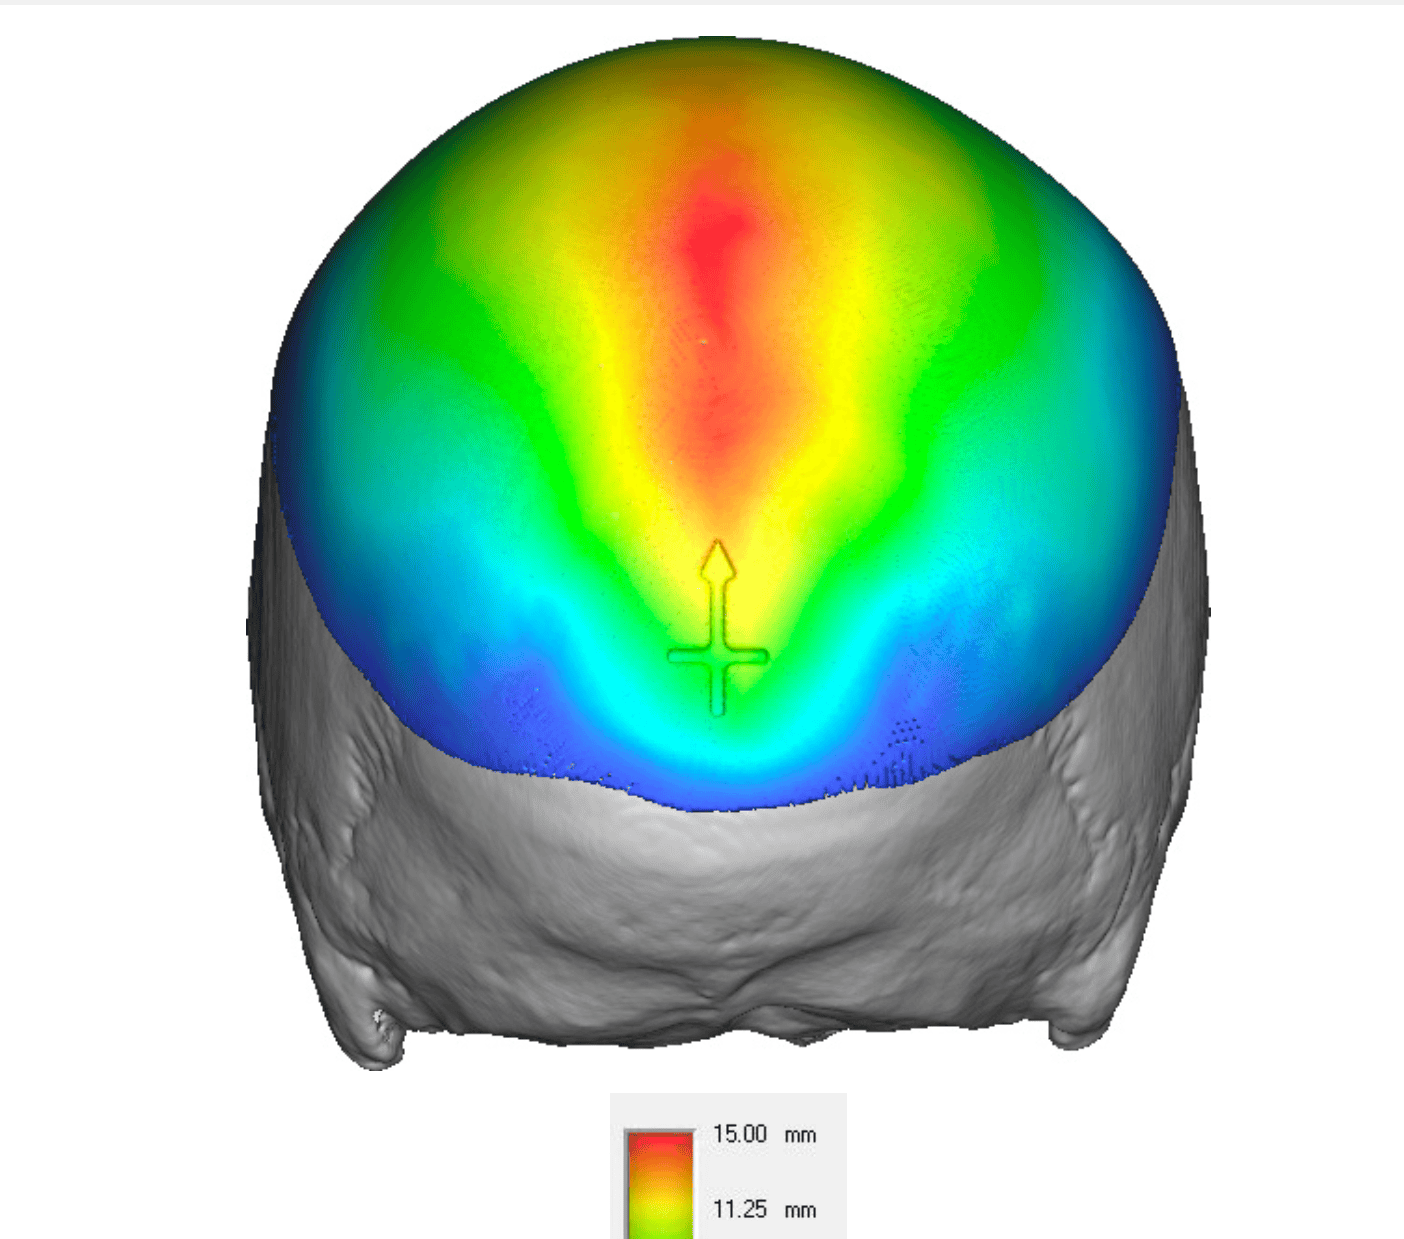

Desire for increased projection of flat back of head.

Placement of a custom skull implant to increase the projection of the back of the head by 15mms and 120ccs of volume.